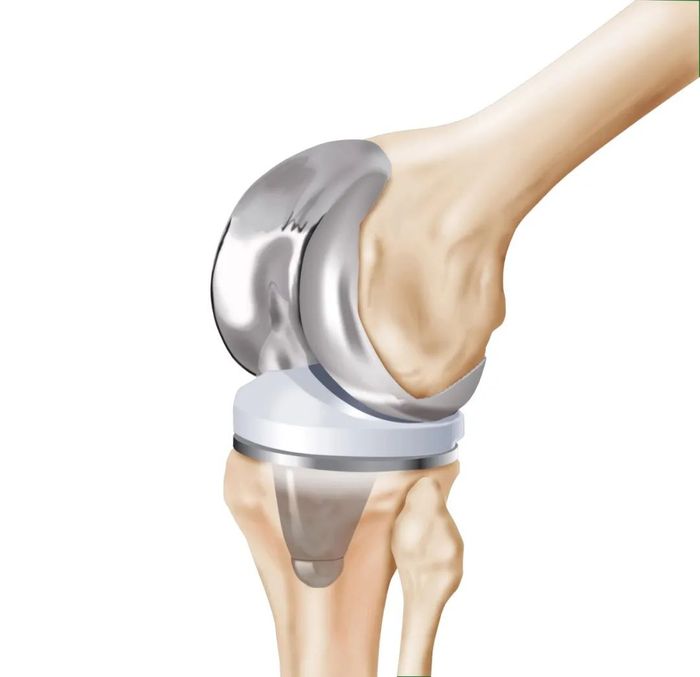

股骨髁植入体毛坯通常为精铸件,材料为铬钴钼,成品公差和表面质量的要求极为严格。在PS型设计的股骨髁植入体中,凸圆、盒区和髁表面关系到植入体的功能性。通常,加工PS型股骨髁的第一步是铣削精铸毛坯,将其加工到非常 “接近最终” 轮廓形状的半成品,然后进行磨削(可5轴磨削或在陶瓷介质中采用拖曳式磨削)及最终的光饰抛光。

膝关节置换手术的成功以及植入体的使用寿命不仅取决于手术的成功,植入体本身的质量也发挥着关键作用。股骨髁表面的制造公差和表面质量至关重要,因此,铣削加工的挑战尤其巨大。即使小缺陷,通常将其称为“暗影”,这些“暗影”的加工面深度差异仅20微米(0.0008英寸)。

股骨髁表面为大曲面,需要与高分子聚乙烯衬垫或“胫骨衬垫”配合,两者曲面的配合需要尽善尽美。如果曲面配合良好,负载就可分布在较大范围上,滑动力则较小。如果曲率不正确,可导致仅点接触,进而导致人工关节提前磨损,最终甚至导致植入体失效。